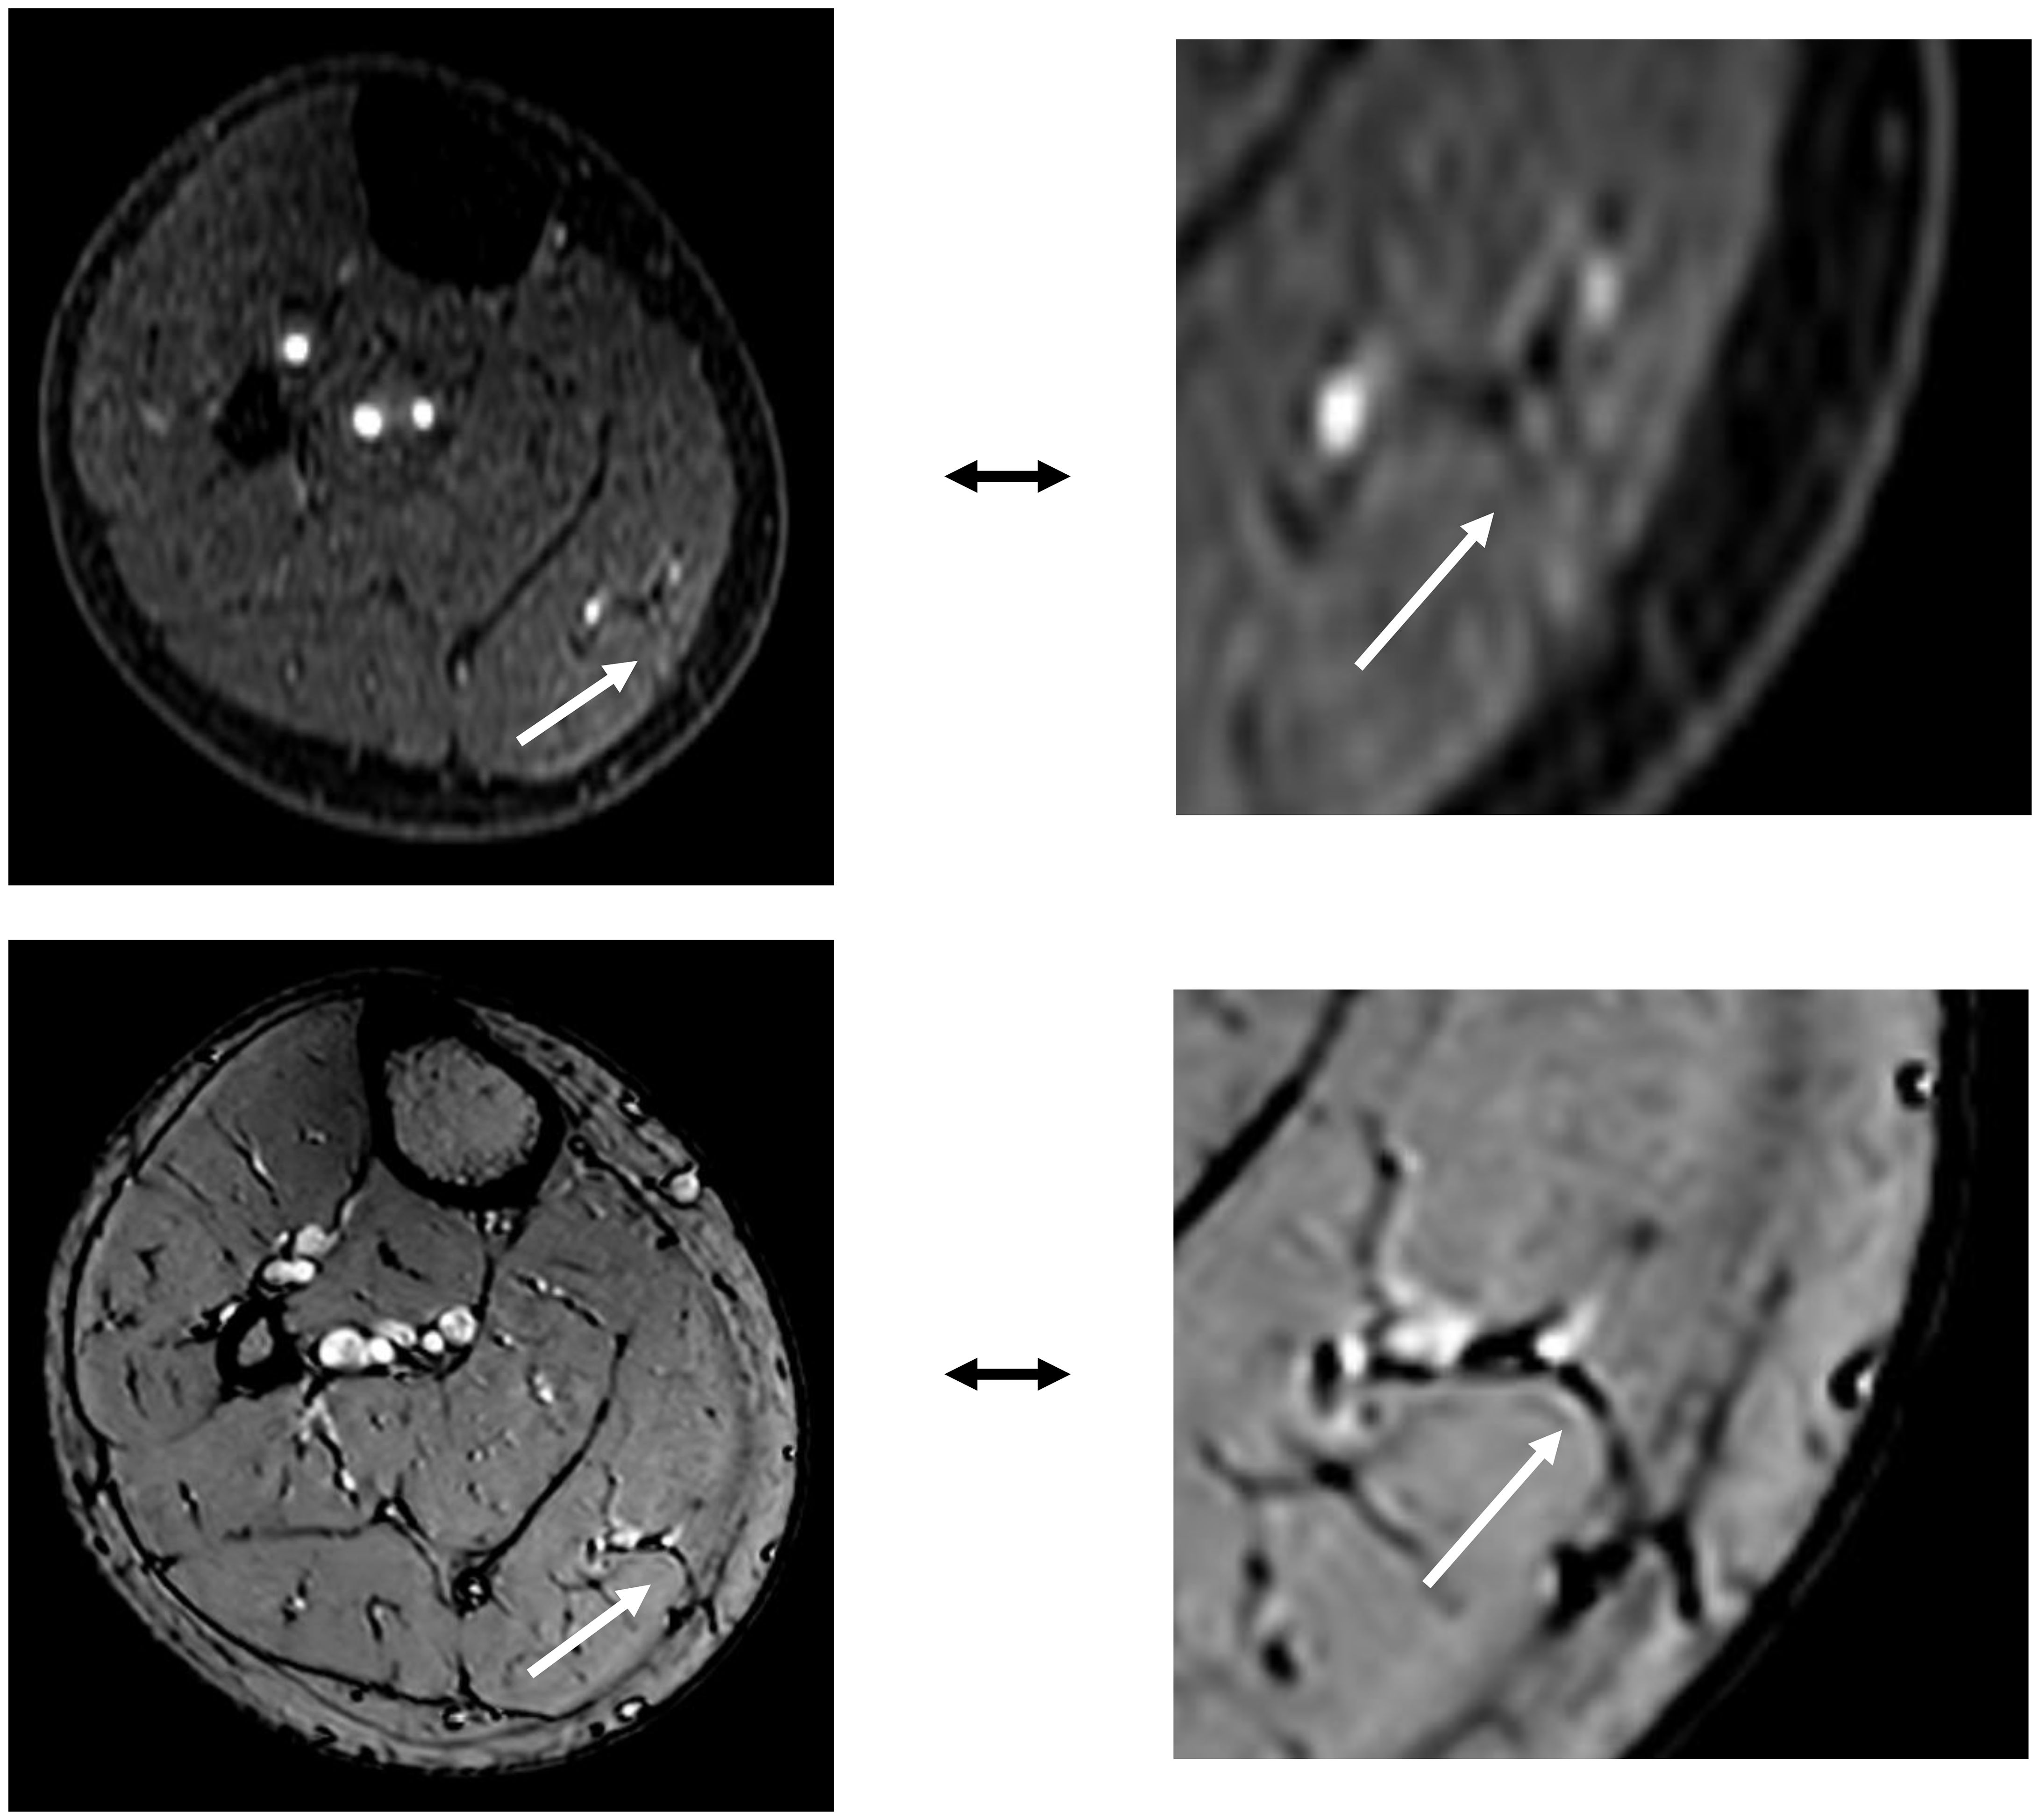

In patients receiving MSAP reconstruction (n=5), 30% of perforators intraoperatively used for flap elevation were visible in CE-mDIXON images. After the first two patients, we hypothesized that fat planes in THRIVE images could give an indication of perforator locations (Figure 8). Therefore, THRIVE images were evaluated in subsequent patients for potential perforators and were incorporated in the 3D model of patient 6. Taking both THRIVE and CE-mDIXON images into consideration, 50% of perforators used for flap elevation were incorporated in the 3D models. In patient 10, the intraoperatively identified perforators were small and not visible on MRA imaging nor incorporated in the 3D model. For perforators that were visible on MRA imaging, all perforators showed an intramuscular course that matched with intraoperative findings.

Figure 8. The top image shows an MSAP perforator as visualized on a contrast-enhanced mDIXON image. The bottom image depicts the same MSAP perforator as a fat plane penetrating the deep fascia, identified on a THRIVE image.